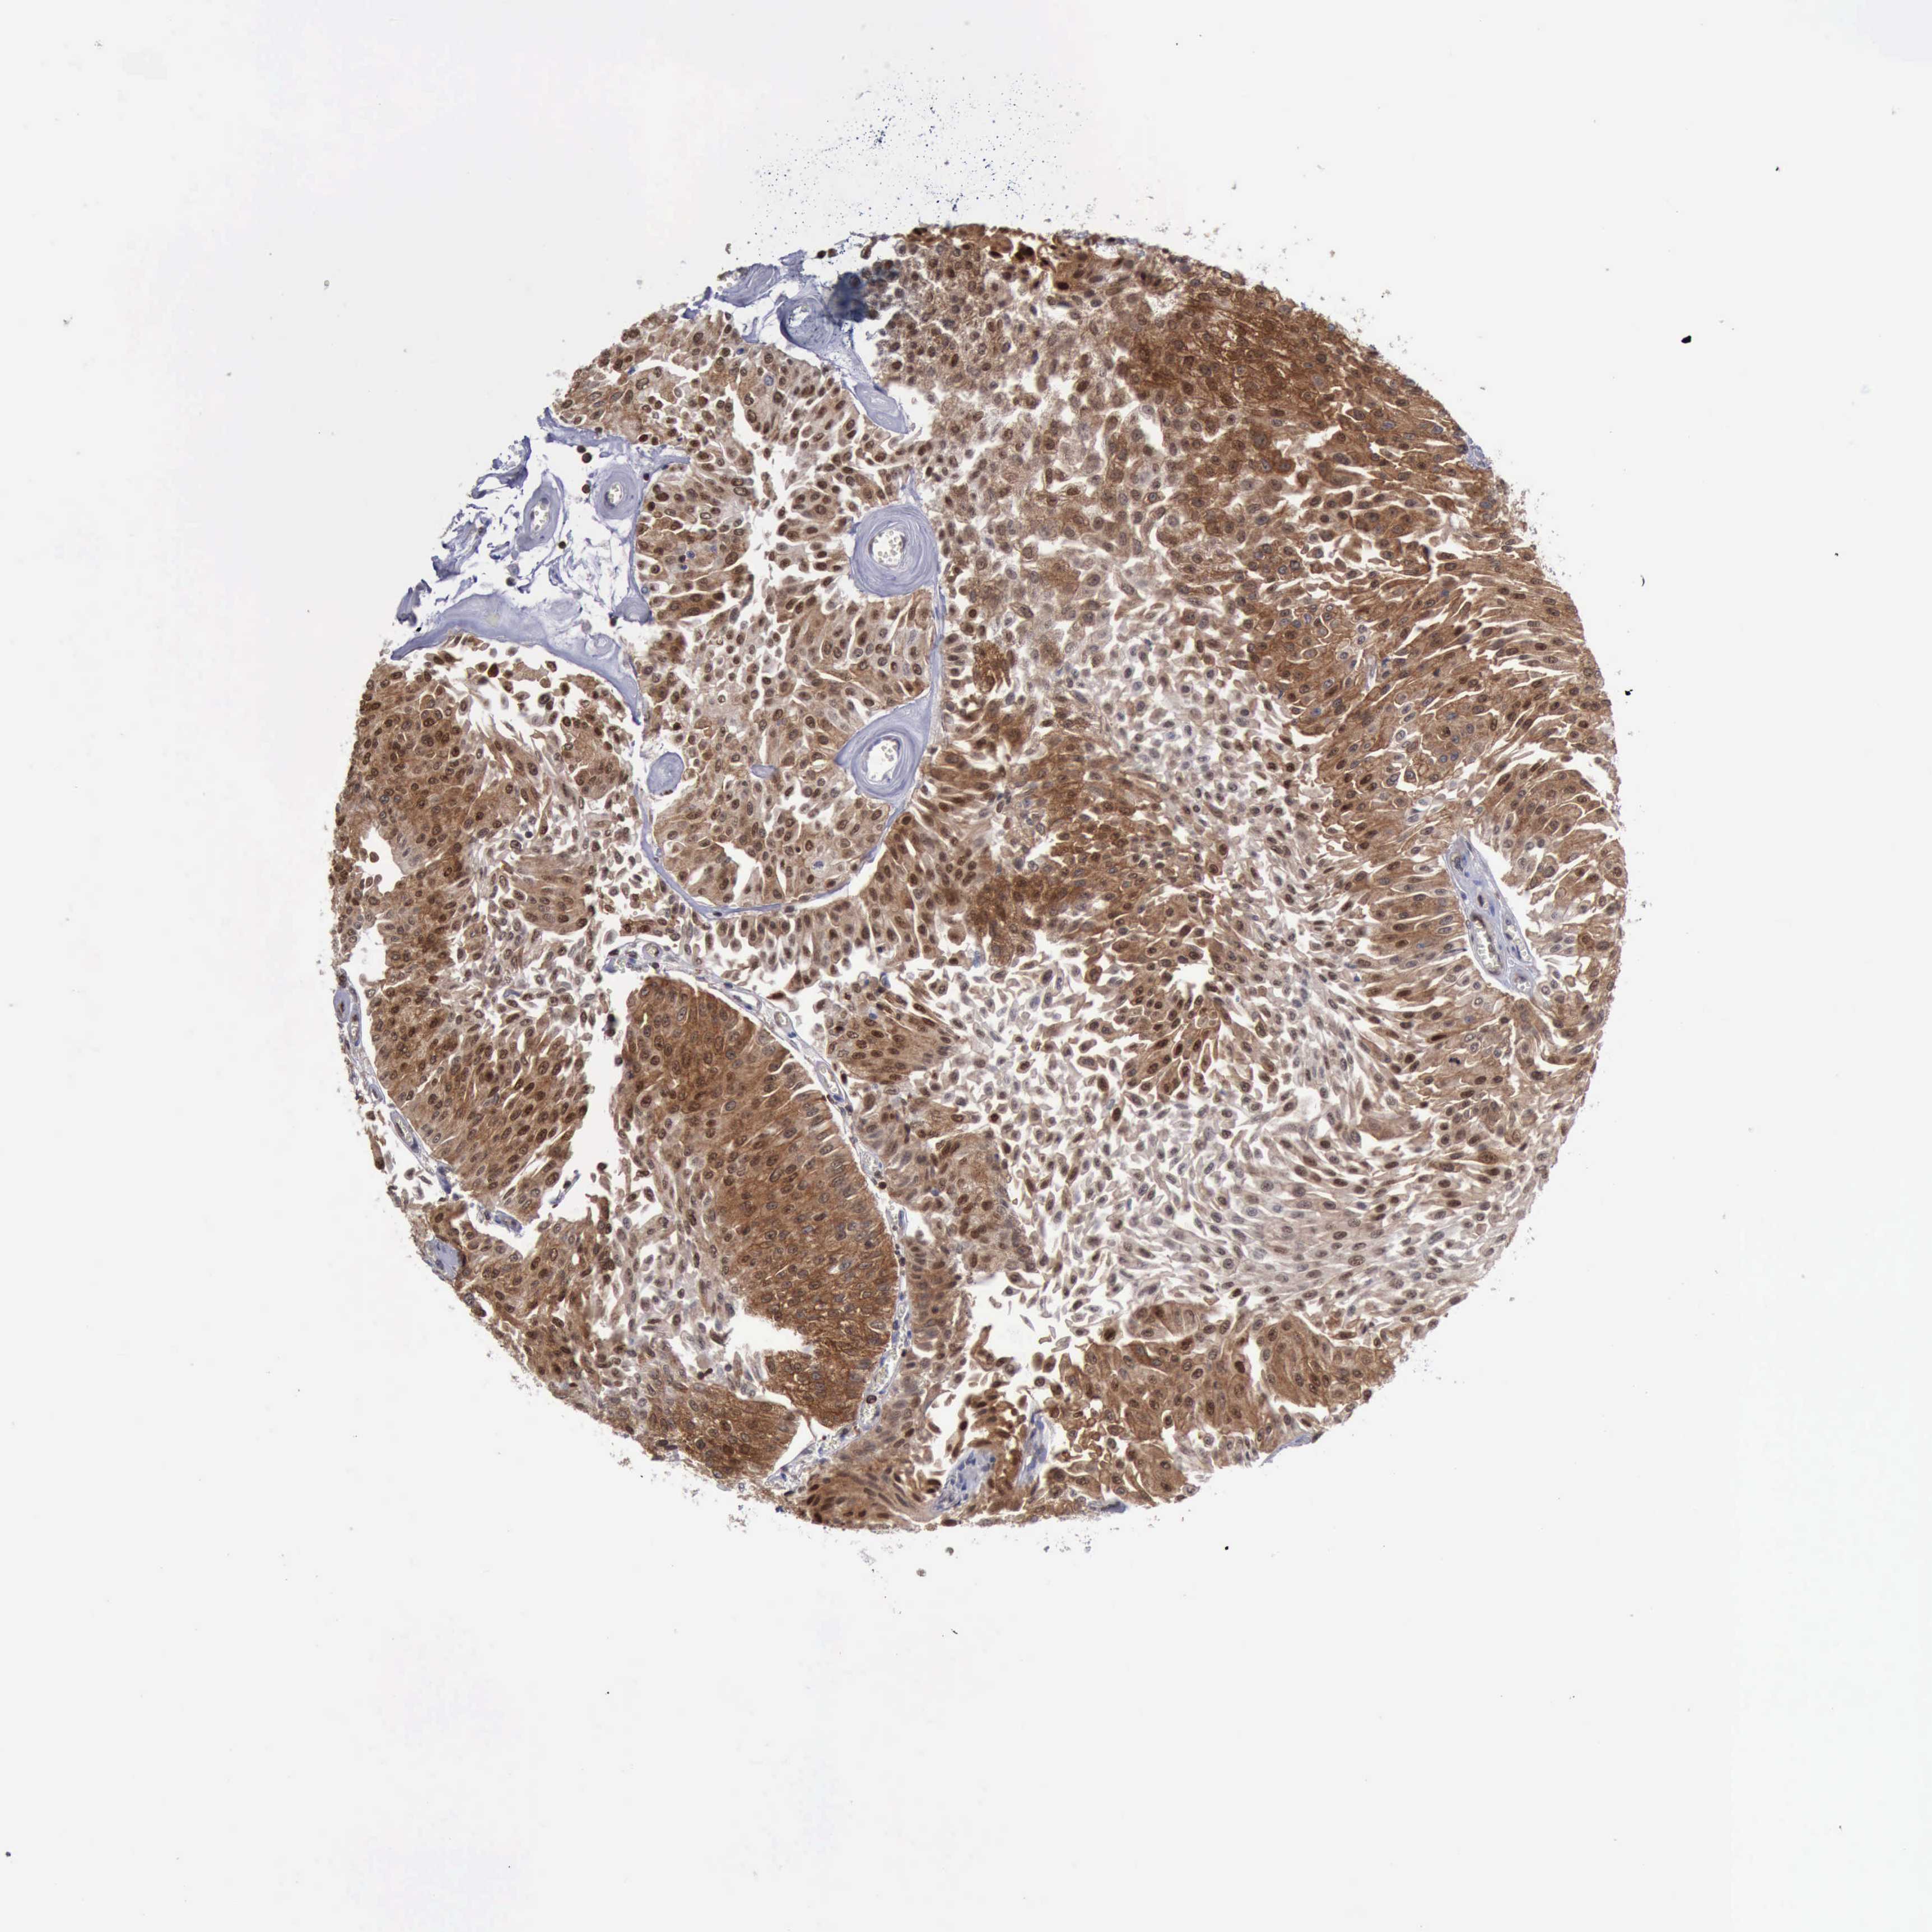

UROTHELIAL CANCER - Protein expressioni

A mouse-over function shows sample information and annotation data. Click on an image to view it in a full screen mode. Samples can be filtered based on level of antibody staining by selecting one or several of the following categories: high, medium, low and not detected. The assay and annotation is described here.

Antibody stainingi

Antibody staining in the annotated cell types in the current human tissue is reported as not detected, low, medium, or high, based on conventional immunohistochemistry profiling in selected tissues. This score is based on the combination of the staining intensity and fraction of stained cells.

Each image is clickable and will lead to virtual microscopy that enables deeper exploration of all samples and also displays staining intensity scores, fraction scores and subcellular localization as well as patient and tissue information for each sample.

Antibody HPA001032

Antibody HPA027214

Antibody CAB037024

Staining

High

Medium

Low

Not detected

Intensity

Strong

Moderate

Weak

Negative

Quantity

>75%

75%-25%

<25%

None

Location

Nuclear

Cytoplasmic/membranous

Cytoplasmic/membranous,nuclear

Urothelial carcinoma, High grade

Urothelial carcinoma, Low grade

Urothelial carcinoma, NOS